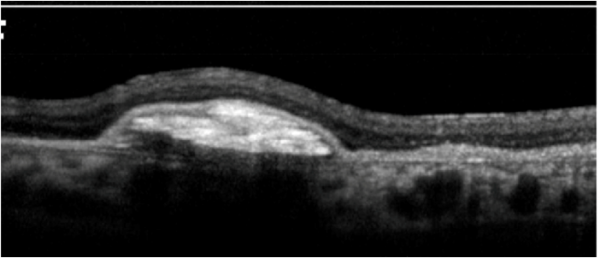

Subretinal hyperreflective material (SHRM) in CNVM:

This SD-OCT feature is identified as hyperreflective material located between the neurosensory retina and retinal pigment epithelium (RPE).

Choroidal Neovascular Membrane (CNVM):

On OCT, CNVM is characterized by subretinal and/or sub-RPE hyperreflective material, sub-RPE hyperreflective columns, RPE tear, or RPE rip. Histopathologically, CNVM (now called macular neovascularization or MNV)[28] has been classified into:

Type 1-CNVM appears beneath the RPE layer and appears as a fibrovascular or hemorrhagic pigment epithelial detachment.

Type 2-CNVM appears above the RPE layer.

Type 3-Neovascularization starts at the retina and progresses posteriorly into subretinal space; eventually, the neovascularization reaches the choroidal circulation and forms retinal-choroidal anastomosis. This is better known as retinal angiomatous proliferation (RAP).